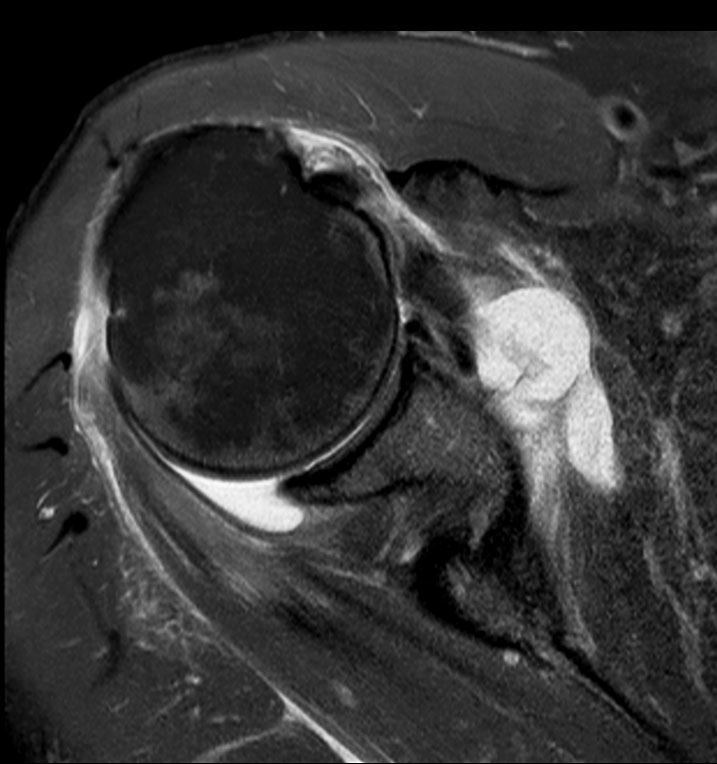

Shoulder imaging using ComforTone